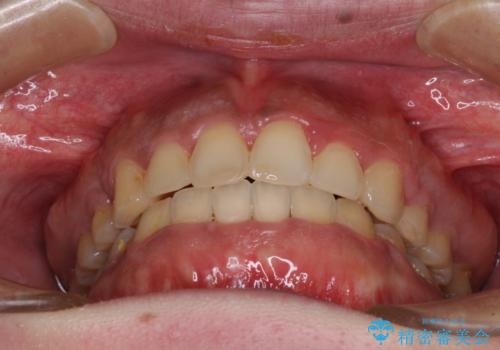

- 口元の突出感と上下前歯のでこぼこを気にして来院された患者様です。

上下前歯部叢生のスペース獲得のため、上下顎左右小臼歯各1歯(計4本)を抜歯して、矯正治療を行うこととしました。

口腔内の清掃性に問題があり、虫歯のリスクが極めて高かったため、短期で治療を終えることを最優先に治療を進めました。